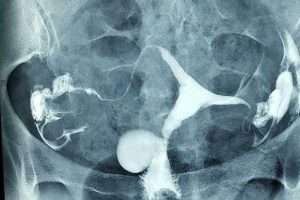

Normal HSG

Normal HSG Filmi